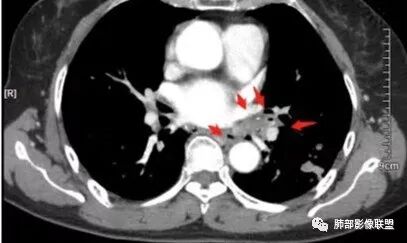

这三幅图是连续的,我们看到支气管中间这一幅狭窄了

大——小——大,狭窄后扩张

从这幅图看好像与周围病灶分界不清,支气管腔狭窄后扩张,支持炎性

今天这个病例有个明显的支气管狭窄,我倾向炎性,主要是和钙化淋巴结相关的,可能是继发的淀粉样变性。到底是什么感染,结核还是其他。我想看看复查后这个淋巴结,有没有突入到支气管腔内,如果有,他是继发于炎症的(比如中叶综合征,就是周围淋巴结压迫支气管,因为钙化淋巴结比较硬,支气管壁扛不住压力,突入支气管腔内,导致管腔狭窄,我们也称为结石征),如果没有,就和淋巴结关系不密切。之前有一例淀粉样变性的,淋巴结弥漫钙化,一种罕见的浆细胞型的CD。